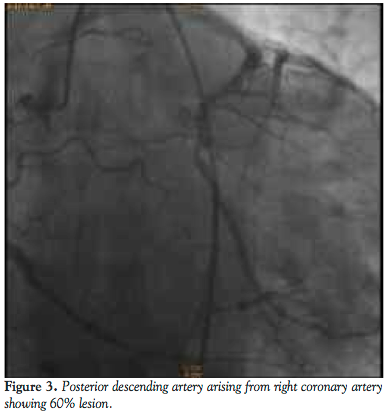

He was admitted for elective cardiac catheterization. Cineangiographic evaluation revealed a single vessel coronary artery arising from the right coronary cusp supplying the entire left system and also the right coronary artery. The right coronary artery was abnormal with significant tortuosity in the proximal and mid segments more consistent with varicose anatomy. Distally the RCA was normal. It gave rise to a posterior descending artery, which had an ostial 60% stenosis. The posterior lateral branch was a small caliber vessel and was normal. The left anterior descending artery (LAD) was a moderate caliber vessel and had no obstructive disease. The first diagonal branch divided into bifurcating branches of which the lower branch had a 70% stenosis. The circumflex artery was a very large caliber vessel that had a proximal 90%-95% stenosis. Left to right collaterals were noted.

In the first case the branching of the left main coronary circuit from the single coronary artery arising from the right coronary cusp illustrates the type IIB1 distribution of coronary arteries.5 The diagnosis was made with coronary angiography and subsequent CT angiography. In this anatomy, the risk of MI, fatal arrhythmias, syncope, and sudden death is no greater than the normal population. In this particular case, the patient required CABG not due to his coronary anomaly but because he had significant coronary artery disease not amenable to a catheter-based intervention. In most instances, this type of coronary anomaly is only diagnosed incidentally when coronary artery angiography is performed. Most of the time, patients have no significant cardiac events related to these types of anomalies.